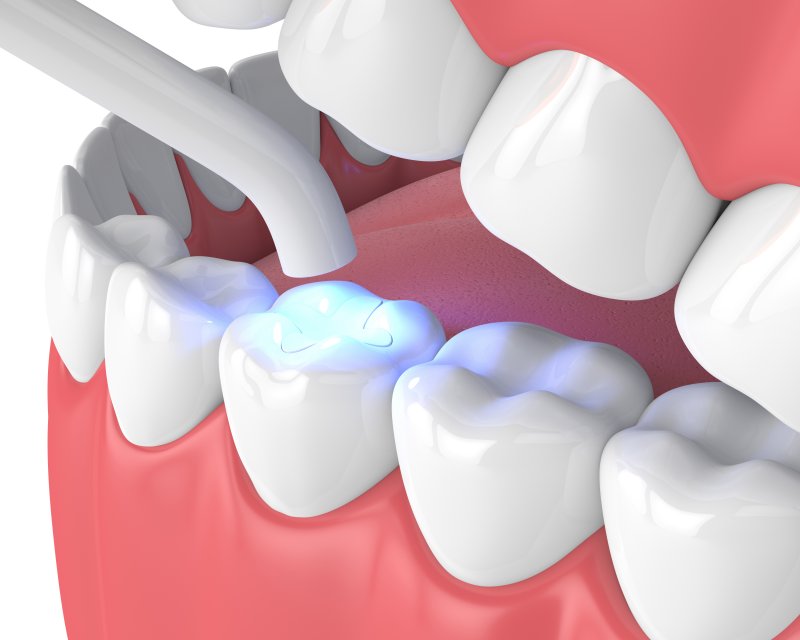

Commonly known as dental fillings, this procedure involves the removal of decayed tooth structure followed by filling the cavity with composite resin to restore its appearance and functionality in terms of biting and chewing. By filling the holes caused by decay and wear, these fillings ensure that teeth remain healthy and can continue to function without the risk of further decay or worsening dental problems.

Composite Fillings

Composite fillings are made up of acrylic resin and finely ground glass-like particles, resulting in restorations that blend seamlessly with the natural appearance of your teeth. These tooth-colored fillings offer both durability and resistance to fractures, making them suitable for small to mid-sized restorations that endure moderate chewing pressure.Porcelain Fillings